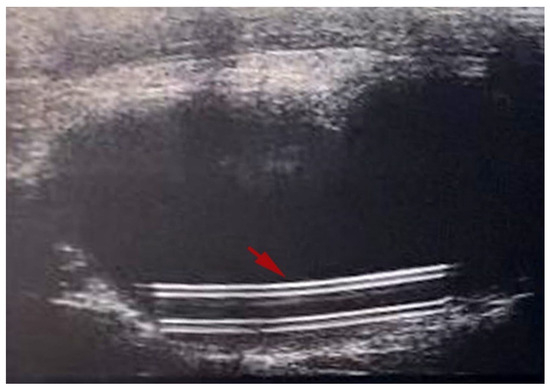

The ultrasound images displayed the catheter well-positioned in situ (Figure 5) in all animals.

Figure 5.

Minimally invasive monitoring made by ultrasound showing the urinary bladder at day 4. The catheter, indicated by the red arrow, appeared well positioned in situ.

Noteworthy, with the aim of reaching the experimental goal while respecting animal welfare, we relied on a minimally invasive imaging procedure, such as ultrasound-guided cystocentesis (Figure 5). On the other hand, as described in a very recent work by Mihai et al., urology has recently reached new frontiers using laparoscopic intraoperative ultrasound. This technique, by allowing high-quality visualization of internal organs, ensures a constant monitoring of the surgical procedure in real-time, enhancing its adequacy and avoiding vascular injuries and superabundant removal of healthy tissue [29]. In the present study, the use of an ultrasound-guided approach allowed us to avoid the use of metabolic cages even for 24 h, corresponding to mild severity according to the Directive 2010/63/EU, with well-established detrimental effects on rodents welfare [30,31], and to assess the anatomical integrity of the urinary bladder as well as the in situ position of the medical device. Remarkably, the ultrasonography enabled us to sample urine under aseptic conditions, necessary to evaluate the efficacy of functionalized catheters at intermediate time points.